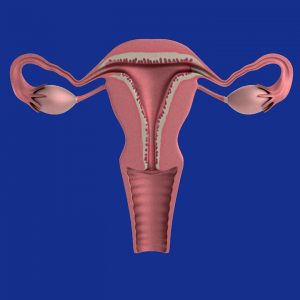

A Gestational Surrogate is a woman who carries a pregnancy with a child who is not genetically related to her. She becomes pregnant through invitro fertilization, with an embryo that includes the father’s (or donor’s) sperm and the mother’s (or donor’s) egg.

Gestational Surrogate (or Gestational Carrier)

A woman who carries and delivers a child without providing her egg, for another couple or person. This term is often abbreviated as GS or GC.

A Traditional Surrogate is a woman who carries a pregnancy with a child who is genetically related to her. She becomes pregnant through Intrauterine Insemination (see definition) using the father’s (or donor’s) sperm.